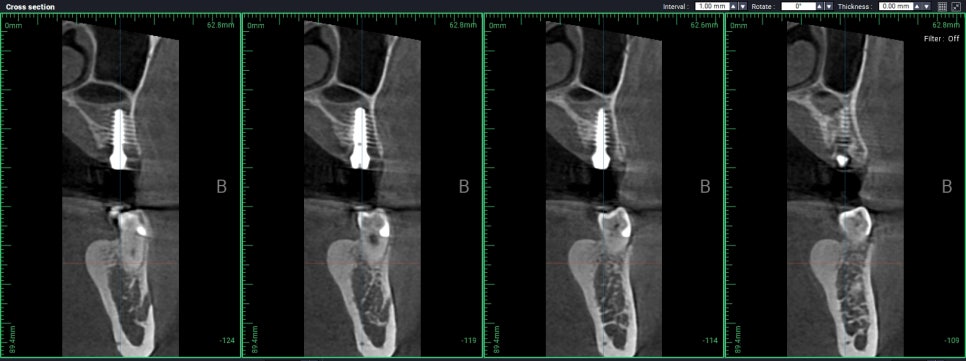

측방접근이 일반적인 선택이겠지만

"최소침습임플란트"를 이용하여

무절개 무봉합으로 측방 상악동 거상술을 대체하고

발치된 자리에 있는 좋은 세포를

최대한 활용하기로 했습니다.